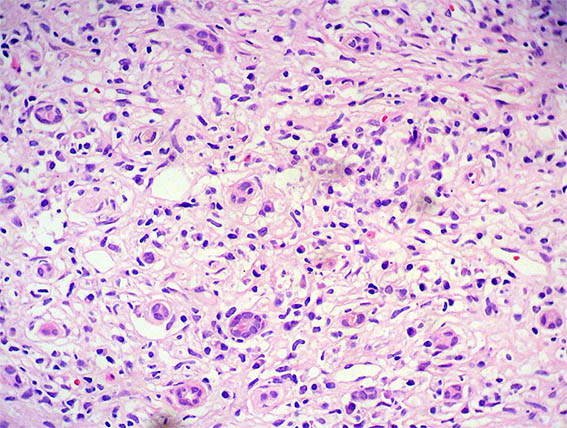

Figura 4. H&E, X400.